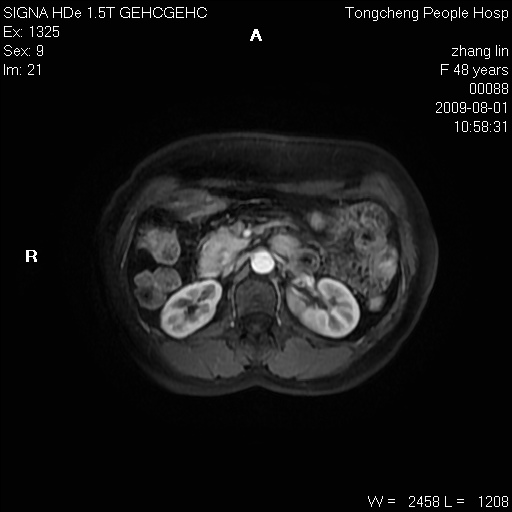

右肾上极见一类圆形病灶,t1wi呈等信号t2wi呈等高混杂信号,三期增强无强化,边界清---考虑囊肿出血。

同反相位均表现为等信号,病变无强化,考虑含蛋白的囊肿可能,弥散加权相或许有些帮助,

肝囊肿

慢性胆囊炎